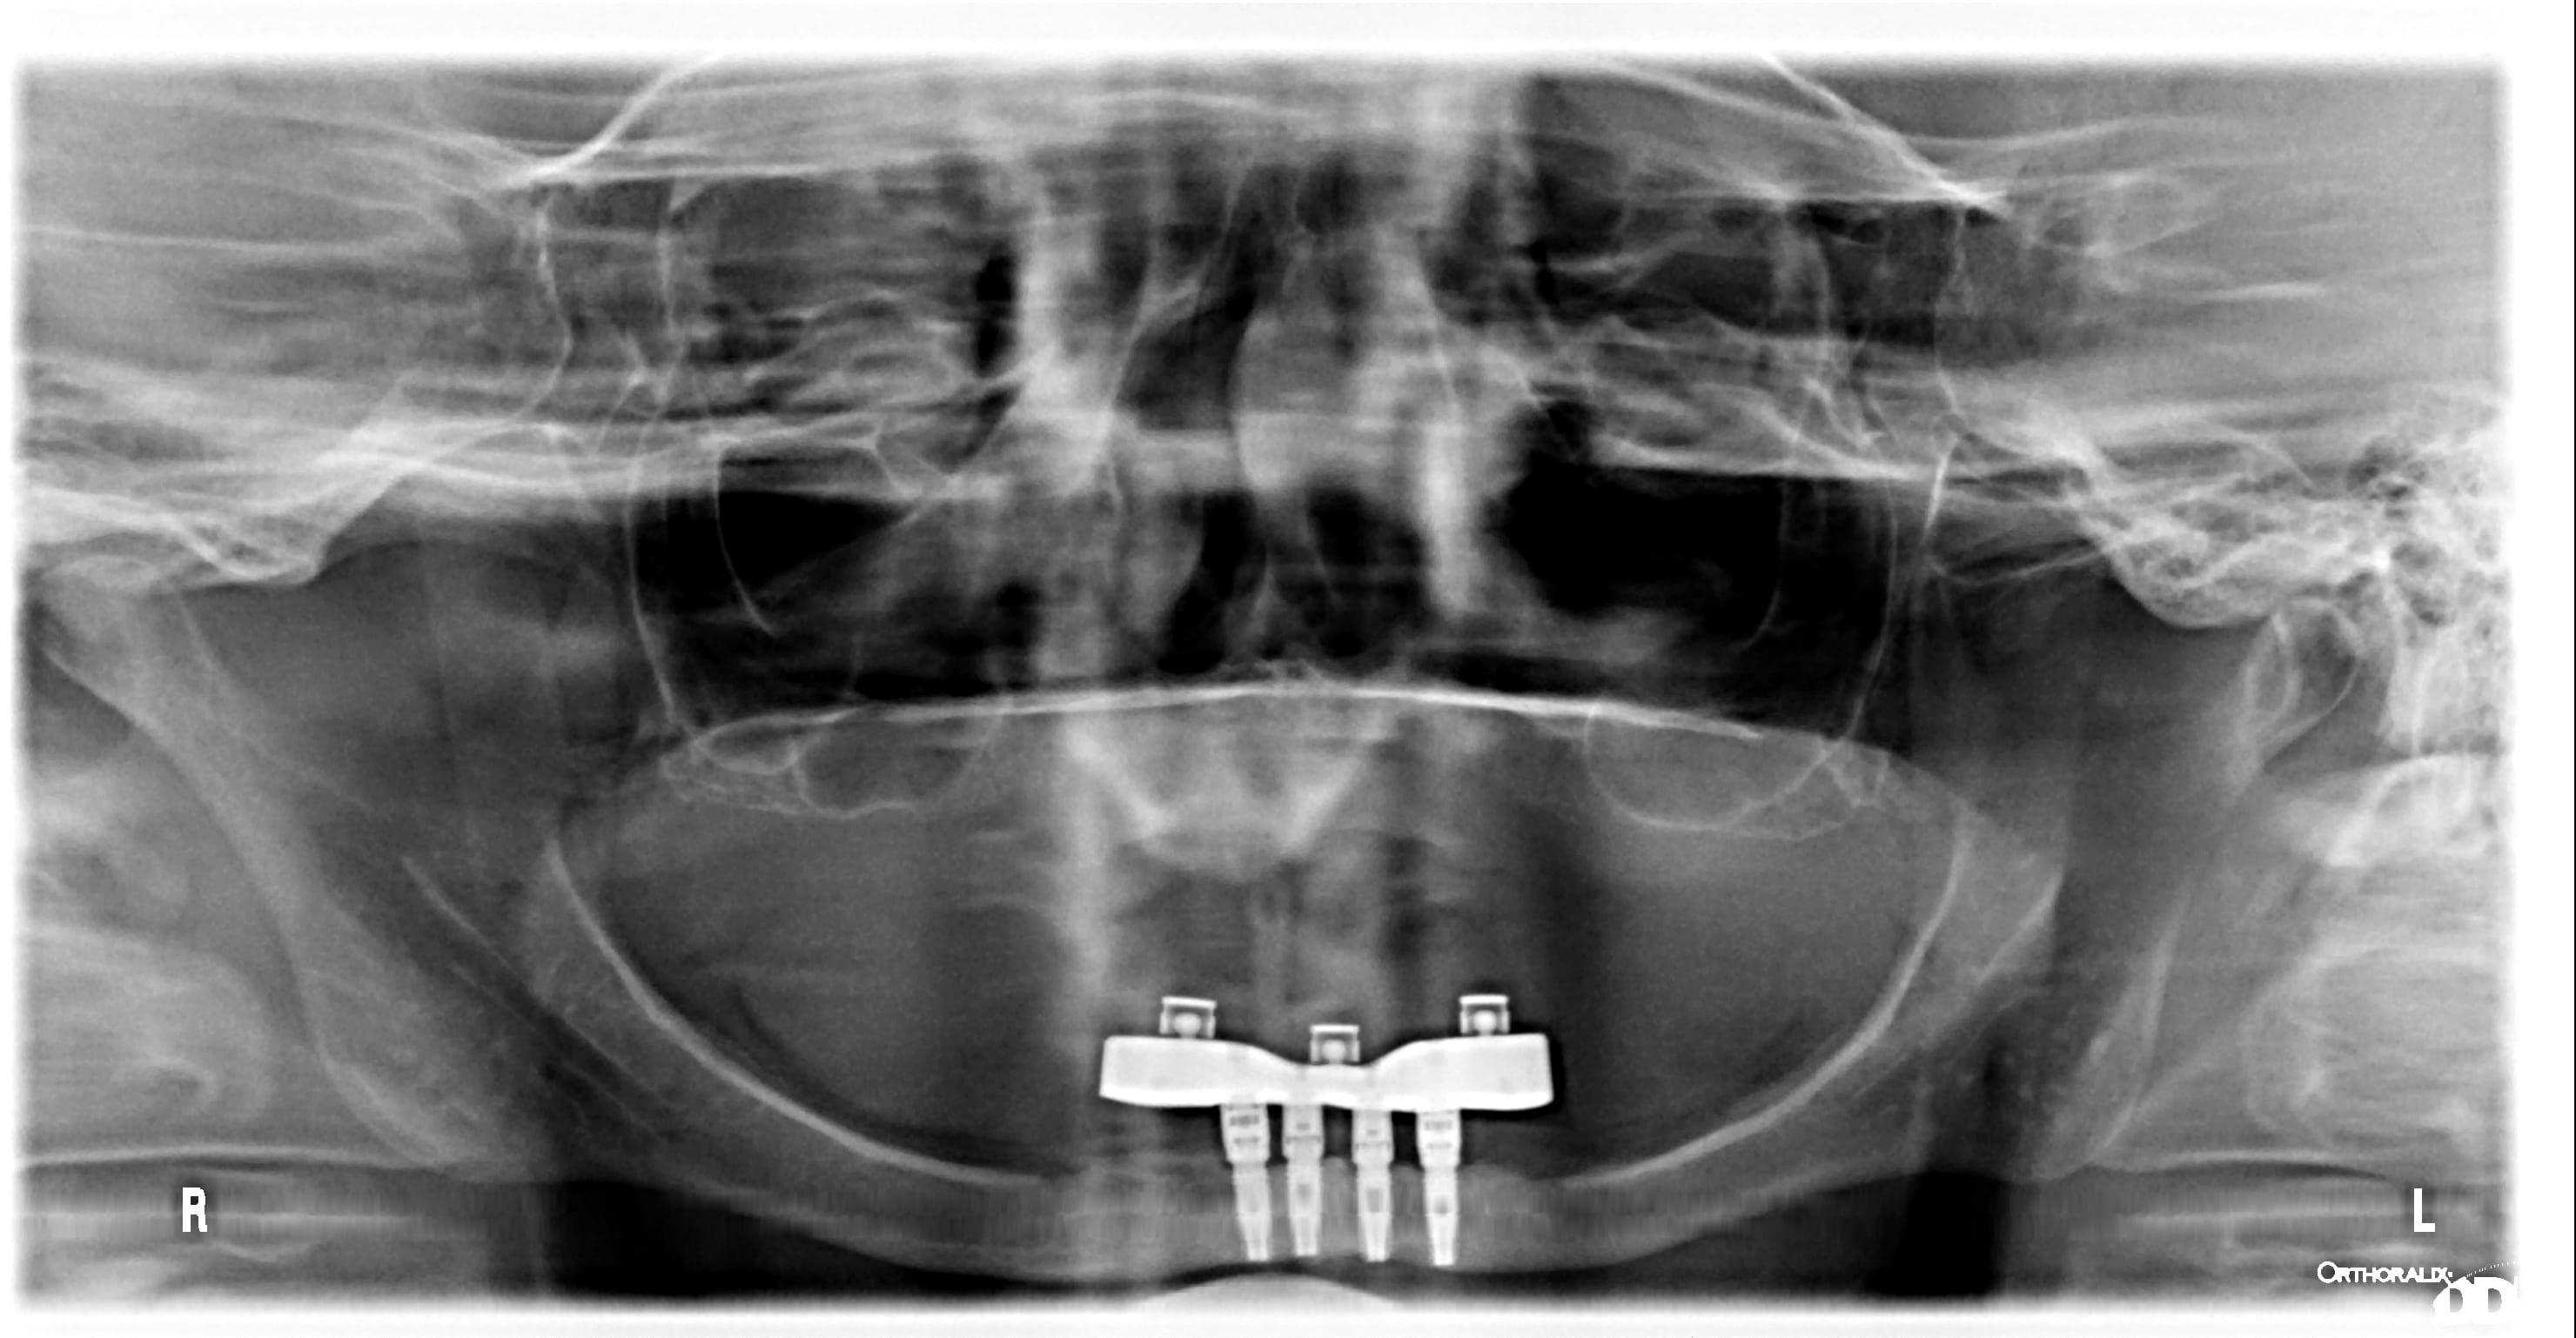

Je refais prothèse sur barre fais au Canada il y a plus de 15 ans avec Implant Branemark MKIII

les piliers transmuqueux ditaux sont de Branemark

la visse de référence de Nobel est Ref. 32983 pour les piliers distaux

Les piliers centraux ne semble pas de nobel

la visse a un diamètre légèrement plus petit au niveau du pas de visse et le diamètre de la tête de la visse que j'ai besoin est de diamètre légèrement inférieur

ci-joint photo de la visse rechercher avec radiographie

la radiio